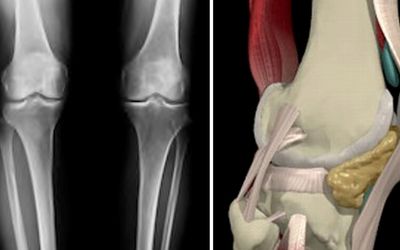

NOTE: The X-ray and MRI photos symbolically illustrate the dramatic difference between these MS languages.

The two pictures on this page illustratively demonstrates the difference between calibration curves (analogue) and SIO (digital). Just like the MRI, the SIO-enabled MS testing data provides the confidence and fidelity that is needed to see the analytical picture clearly whether it is for diagnosis or therapy monitoring. Our platform is also very valuable when it is used for companion diagnostic testing in drug development by shortening the biologic drug development resulting in huge savings. When biologic drugs reach the market faster, stratified patients win by selecting more effective, targeted therapeutic treatments.